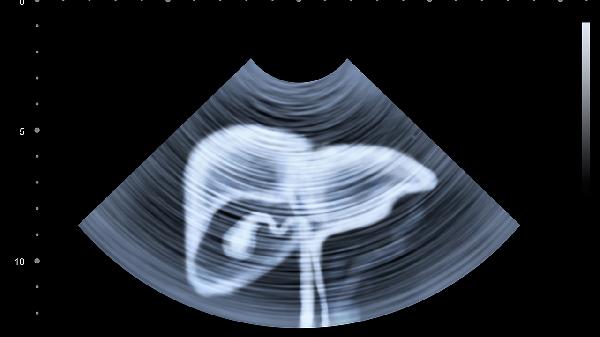

转氨酶轻度升高且无其他异常指标时,通常优先考虑病毒性肝炎、脂肪肝等常见病因,可通过肝功能复查、超声等基础检查明确。若患者存在长期饮酒史、乙肝携带等高危因素,或转氨酶持续异常超过3个月,肝脏弹性成像有助于评估肝纤维化程度。该检查对慢性肝病分期具有重要价值,能辅助鉴别肝硬化早期改变。

急性药物性肝损伤或一过性转氨酶升高患者,可能无须立即进行弹性成像。妊娠期、严重腹水或肥胖人群可能影响检测准确性,需医生综合评估。部分非肝源性疾病如心肌炎、肌营养不良也可导致转氨酶异常,此时应针对原发病检查。